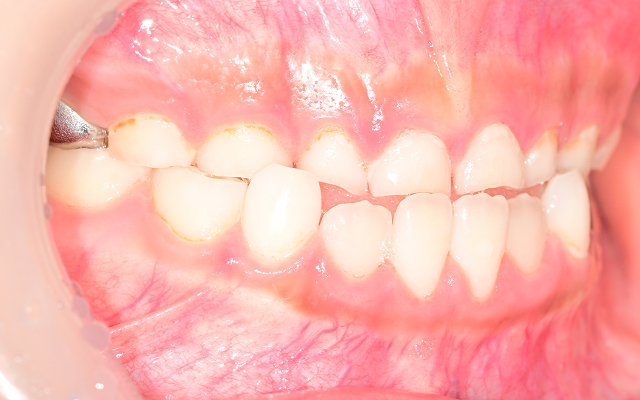

• 04

입으로 호흡하는 습관이 고착되어 얼굴형이 길어짐